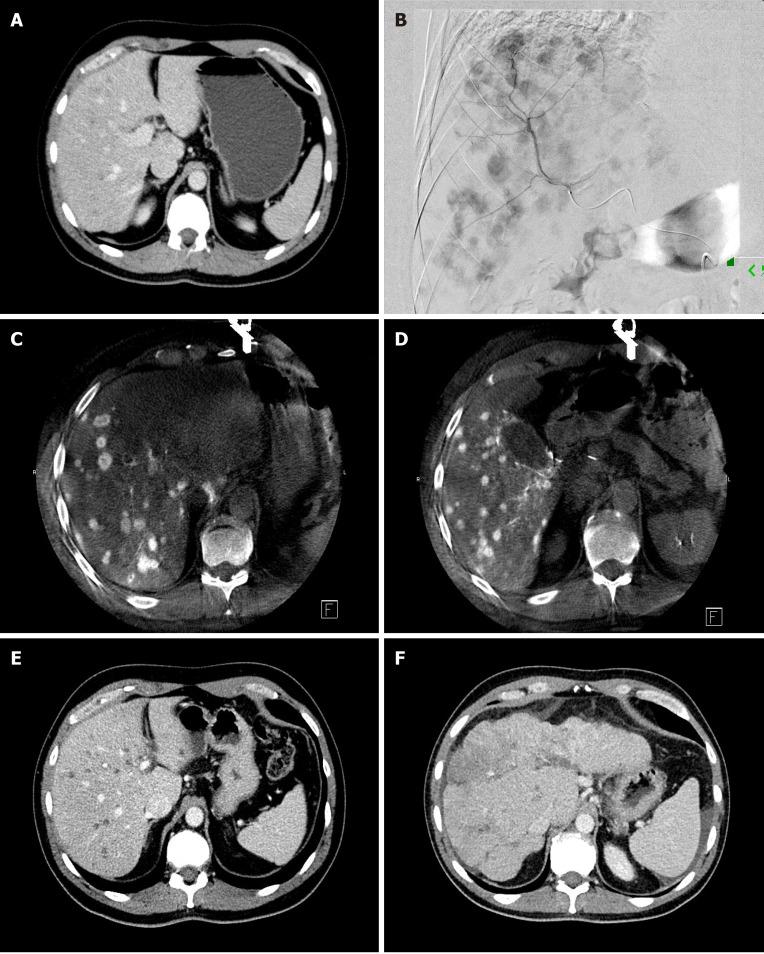

原发性和转移性胰腺癌的微创影像引导治疗。

Minimally invasive image-guided therapy of primary and metastatic pancreatic cancer.

Pancreatic cancer is a challenging malignancy with limited treatment options and poor life expectancy. The only curative option is surgical resection, but only 15%-20% of patients are resectable at presentation because more than 50% of patients has distant metastasis at diagnosis and the rest of them has locally advanced pancreatic cancer (LAPC). The standard of care first line treatment for LAPC patients is chemotherapy with or without radiation therapy. Recent developments in minimally invasive ablative techniques may add to the treatment armamentarium of LAPC. There are increasing number of studies evaluating these novel ablative techniques, including radiofrequency ablation, microwave ablation, cryoablation and irreversible electroporation. Most studies which included pancreatic tumor ablation, demonstrated improved overall survival in LAPC patients. However, the exact protocols are yet to set up to which stage of the treatment algorithm ablative techniques can be added and in what kind of treatment combinations. Patients with metastatic pancreatic cancer has dismal prognosis with 5-year survival is only 3%. The most common metastatic site is the liver as 90% of pancreatic cancer patients develop liver metastasis. Chemotherapy is the primary treatment option for patients with metastatic pancreatic cancer. However, when the tumor is not responding to chemotherapy or severe drug toxicity develops, locoregional liver-directed therapies can provide an opportunity to control intrahepatic disease progression and improve survival in selected patients. During the last decade new therapeutic options arose with the advancement of minimally invasive technologies to treat pancreatic cancer patients. These new therapies have been a topic of increasing interest due to the severe prognostic implications of locally advanced and metastatic pancreatic cancer and the low comorbid risk of these procedures. This review summarizes new ablative options for patients with LAPC and percutaneous liver-directed therapies for patients with liver-dominant metastatic disease.

胰腺癌是一种具有挑战性的恶性肿瘤,治疗选择有限,预期寿命短。唯一的治愈方法是手术切除,但只有 15%-20%的患者在就诊时可切除,因为超过 50%的患者在诊断时已经发生远处转移,其余患者则患有局部晚期胰腺癌(LAPC)。LAPC 患者的一线治疗标准是化疗联合或不联合放疗。微创消融技术的最新进展可能为 LAPC 的治疗手段增添新方法。越来越多的研究评估了这些新的消融技术,包括射频消融、微波消融、冷冻消融和不可逆电穿孔。大多数包含胰腺肿瘤消融的研究表明,LAPC 患者的总生存期得到改善。然而,确切的方案仍有待确定,消融技术可以添加到治疗算法的哪个阶段,以及哪种治疗组合中。转移性胰腺癌患者预后极差,5 年生存率仅为 3%。最常见的转移部位是肝脏,因为 90%的胰腺癌患者会发生肝转移。化疗是转移性胰腺癌患者的主要治疗选择。然而,当肿瘤对化疗无反应或出现严重的药物毒性时,局部肝脏导向治疗可以为控制肝内疾病进展和改善选定患者的生存提供机会。在过去十年中,随着微创技术的进步,出现了治疗胰腺癌患者的新治疗选择。这些新的治疗方法引起了越来越多的关注,因为局部晚期和转移性胰腺癌的预后严重,这些手术的合并症风险低。本文综述了 LAPC 患者的新消融选择以及肝优势转移性疾病患者的经皮肝脏导向治疗。